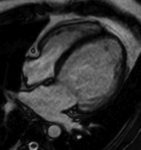

症例

前壁中隔心筋梗塞症例)黒く描出された正常心筋に対し、 前壁中隔内膜側に遅延造影像を認め、心筋梗塞による障害心筋の評価が可能です。

(拡張型心筋症)左室の拡張と中隔に線状の遅延造影像を認めます。

(心臓サルコイドーシス)前壁~中隔外膜側に遅延造影像を認め、原疾患により障害を受けて線維化した心筋を認めます。